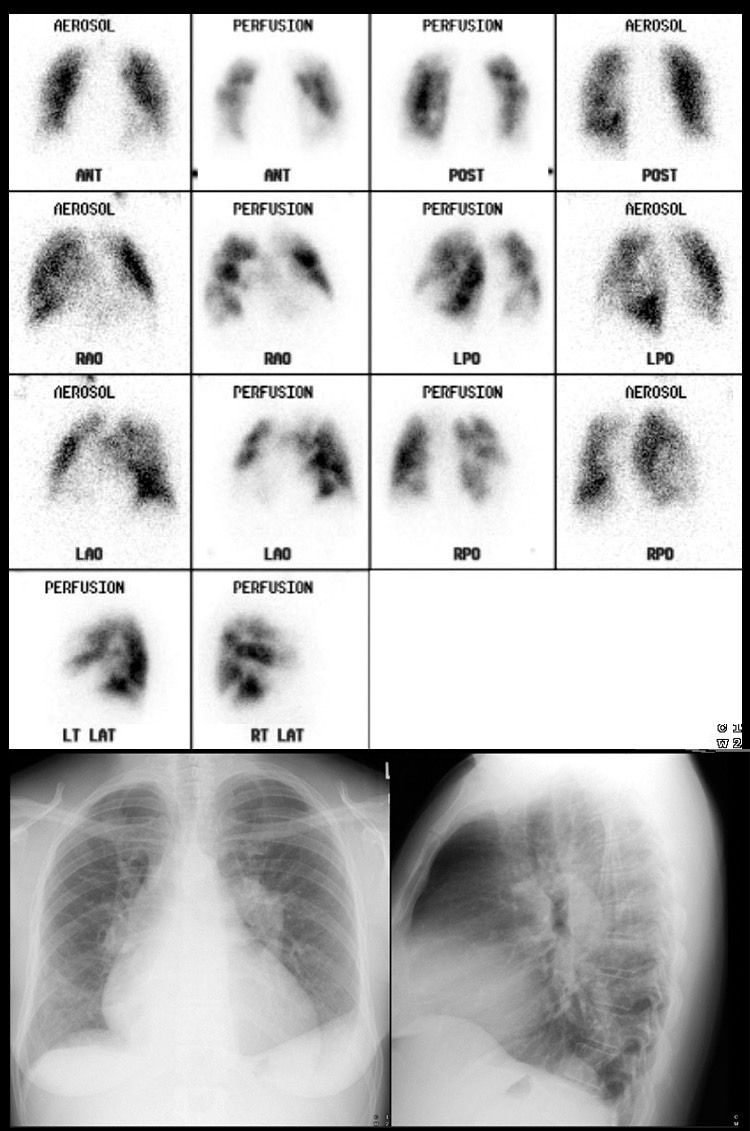

Repeat VQ scan performed eight weeks after childbirth when patient was What Happens During A Vq Scan If you get both, one scan. A vq scan is short for lung or pulmonary ventilation (v) and perfusion (q) scans. V/q scans are usually performed in a radiology clinic or a hospital. One of the most common indications for a v/q scan is suspected pulmonary embolism i.e. What happens during the test. Pulmonary ventilation (v) and perfusion (q) scan,. What Happens During A Vq Scan.

VQ scan of lung What Happens During A Vq Scan Pulmonary ventilation (v) and perfusion (q) scan, also known as lung v/q scan, is a nuclear test that uses the perfusion scan to delineate the blood flow distribution and the ventilation. What happens during a v/q scan? It’s an imaging test that measures air and blood. For the perfusion scan, a technician will set up an. A vq scan is. What Happens During A Vq Scan.